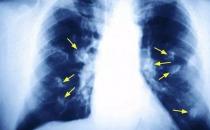

血栓通俗地说就是“血块",它像塞子一样堵塞了身体各部位血管的通道,导致相关脏器没有血液供应,造成突然死亡。血栓在脑部血管产生就导致脑梗,在冠状动脉产生就形成心梗,堵塞到肺部就是“肺栓塞”。

大多数血栓形成后、发病前,是没有任何症状及感觉的,甚至到医院心脑血管专科做常规检查,血脂、血压、心电图、CT等一切都显示指标正常。特别需要指出的是,目前心房颤动引起的血栓问题越来越多。心房颤动(简称“房颤”),是一种心律失常疾病,心房失去了正常的收缩功能,此时在心房的角落容易有血栓沉积,这些血栓可以随时脱落,顺着血流进入大脑造成脑梗,跑到腹部动脉,造成肠坏死等严重后果。但是公众不了解房颤需要抗血栓治疗,等到发生栓塞,一切都晚了。因此建议房颤患者定期到血栓专家门诊就诊,进行评估和治疗。